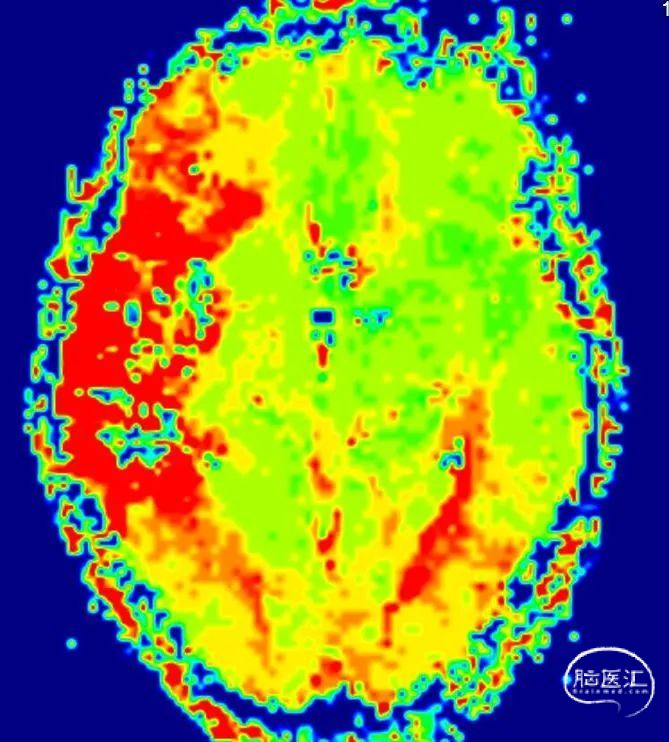

MR灌注

CBV